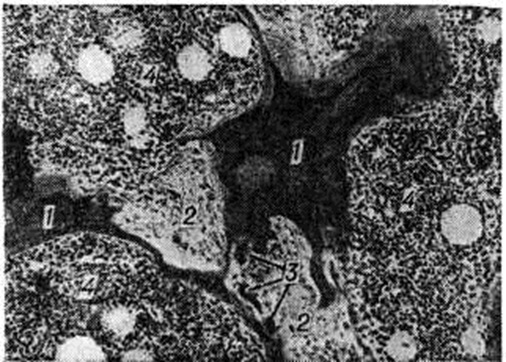

Диафизы длинных трубчатых костей умеренно дугообразно искривляются. Грудная клетка может по форме напоминать колокол, физиологический изгибы позвоночника усиливаются. Позвонки могут принимать вид рыбьих позвонков, а таз — карточного сердца. Патологический переломы костей при Паратиреоидная остеодистрофия обычно медленно срастаются, так как костная мозоль долго не созревает. В случаях Паратиреоидная остеодистрофия при гормонально малоактивных аденомах паращитовидных желёз макроскопические изменения в костях минимальные или вообще не выявляются. Аналогичная картина наблюдается в начальном периоде Паратиреоидная остеодистрофия Однако микроскопическое исследование костей и в таких случаях обнаруживает характерные изменения. При микроскопическом исследовании в случаях выраженной Паратиреоидная остеодистрофия выявляется интенсивное остеокластическое рассасывание предсуществующих костных структур (рисунок 3). Значительно активизируется костеобразование. Новообразованные костные структуры отличаются незрелостью (рисунок 4) и уменьшенным содержанием минерального компонента, что документируется микрорентгенографией (смотри полный свод знаний). В результате перестройки компактное вещество трубчатых костей теряет компактную организацию и становится спонгиозированным (рисунок 4). Исчезает чётко выраженная в норме граница между компактным и губчатым веществом кости. Характерным для Паратиреоидная остеодистрофия является массивное разрастание в межкостных пространствах (в межбалочных пространствах губчатого вещества и в расширенных гаверсовых каналах компактного) клеточно-волокнистой ткани, на основе которой происходит новообразование костных структур (рисунок 3, 4). А. В. Русаков доказал, что эта ткань является производной эндоста, то есть дериватом остеогенных элементов, а не кроветворных (нередко употребляемое наименование этой ткани «фиброзный костный мозг» нельзя считать правильным). В ходе перестройки рассасыванию подвергаются и новообразованные костные структуры, в свою очередь замещаемые новыми, часто ещё более примитивными. Несмотря на интенсивную перестройку, костная ткань не теряет функциональной архитектоники. Исключение составляют зоны с наличием опухолевидных разрастаний и кист. Эти разрастания по гистологический структуре идентичны истинным опухолям — остеобластокластомам (смотри полный свод знаний), но в отличие от последних являются реактивными и исчезают при ликвидации гиперпаратиреоза (после удаления опухоли паращитовидной железы). В лёгких случаях заболевания, то есть при гормонально малоактивной аденоме паращитовидной железы, признаки повышенной перестройки чётко выявляются, в частности, по наличию многочисленных «обломочных» структур и линий склеивания, свидетельствующих о многократных чередованиях процессов рассасывания и образования костного вещества. В ряде случаев при Паратиреоидная остеодистрофия наблюдается отложение солей кальция (смотри полный свод знаний: Кальциноз) в желудочно-кишечные тракте, лёгких, почках. В последнем случае возможно развитие выделительного нефроза, нефрокальциноза или калькулёзного пиелонефрита с явлениями почечной недостаточности. При гистохимическом исследовании костной ткани при Паратиреоидная остеодистрофия в ней обнаруживают довольно много (по сравнению со зрелой костной тканью) нейтральных и несколько меньше кислых мукополисахаридов (гликозаминогликанов). Клиническая картина. Проявляется Паратиреоидная остеодистрофия болями в костях и суставах. На ранних стадиях заболевания местные изменения могут отсутствовать или выражаться в виде припухлостей в области поражённых костей. В дальнейшем наблюдаются патологический переломы (смотри полный свод знаний) костей (могут быть многократными), приводящие к грубым деформациям скелета. Иногда на месте переломов возникают ложные суставы (смотри полный свод знаний). При активизации процесса происходит почти полное рассасывание отдельных сегментов кости. Паратиреоидная остеодистрофия обычно сопровождается изменениями в сердечнососудистой, выделительной, пищеварительной, нервной системах. В некоторых случаях в области щитовидной железы прощупывают утолщение — аденому паращитовидных желёз. Осложнения. У больных с нефрокальцинозом может развиться почечная колика и острая почечная недостаточность (смотри полный свод знаний) в результате закупорки мочеточника камнем, ацидоз (смотри полный свод знаний), вторичный гиперпаратиреоз, развитие которого связано с нарушением функции почек. Диагноз основан на характерной клинические, картине: боли в костях, патологический переломы, деформации скелета, рост костной «опухоли» у истощённого, ослабленного, адинамичного больного с сухой кожей, страдающего жаждой, полиурией, диспептическими и дизурическими явлениями, имеющего в анамнезе почечную колику. Чаще больной акцентирует внимание на какой-либо одной жалобе, что может быть причиной ошибочной диагностики, особенно в ранней фазе Паратиреоидная остеодистрофия Биохимический исследование крови и мочи больного способствует установлению правильного диагноза. Биохимический изменения выражаются высоким содержанием кальция и щелочной фосфатазы и низким содержанием фосфора в сыворотке крови, повышенным выделением с мочой кальция, фосфора, аминоазота и оксипролина. В сомнительных случаях, при неясных клинико-рентгенологических данных, определяют паратгормон крови, а также проводят радиоизотопное исследование паращитовидных желёз с селенметионином (смотри полный свод знаний: Паращитовидные железы) и термографию (смотри полный свод знаний). Начальные изменения в костях проявляются на рентгенограммах патологической перестройкой костного вещества пока ещё без нарушения формы костей. Эта перестройка выражается исчезновением однородности компактного вещества диафиза и его разволокнением. Эндостальная поверхность изображается нечётко. В участках с преобладанием губчатого вещества кости определяется неравномерное мелкоочаговое разрежение в виде густо расположенных, частично сливающихся между собой без чётких контуров очажков. В отдельных местах скелета могут обнаруживаться довольно крупные участки бесструктурного разрежения. Изменения не бывают строго симметричными, но они проявляются, как правило, в обеих половинах скелета и во многих костях. В черепе изменения могут выражаться истончением костей и смазанностью их структуры либо утолщением костей и структурным рисунком, характерным для рентгенологическое картины болезни Педжета (рисунок 5). В развитой стадии болезни отдельные очаги в трубчатых костях имеют сходство с очагами при местной фиброзной остеодистрофии, но они значительно разнообразнее и сложнее. К кистозно-очаговым структурным изменениям кости и к веретенообразному её утолщению присоединяются деформации статического характера: в трубчатых костях они выражаются дугообразным искривлением, а в костях таза изменением входа в малый таз в форме так называемый карточного сердца. Характерна деформация верхнего конца бедренной кости в виде так называемый пастушьей палки (рисунок 6). Не менее показательна деформация грудной клетки, которая вследствие западения средних рёбер обеих её половин внутрь (из-за бывших множественных патологический переломов) по форме напоминает колокол. Более наглядным доказательством бывшего патологический перелома или переломов в одной трубчатой кости служит угловое искривление продольной её оси. Одним из признаков Паратиреоидная остеодистрофия является лоозеровская зона перестройки, возникающая обычно на выпуклой стороне дугообразно изогнутой длинной трубчатой кости, но встречающаяся иногда и при отсутствии искривления. Зоны перестройки определяются также в костях таза, в периферических трубчатых и в других костях.